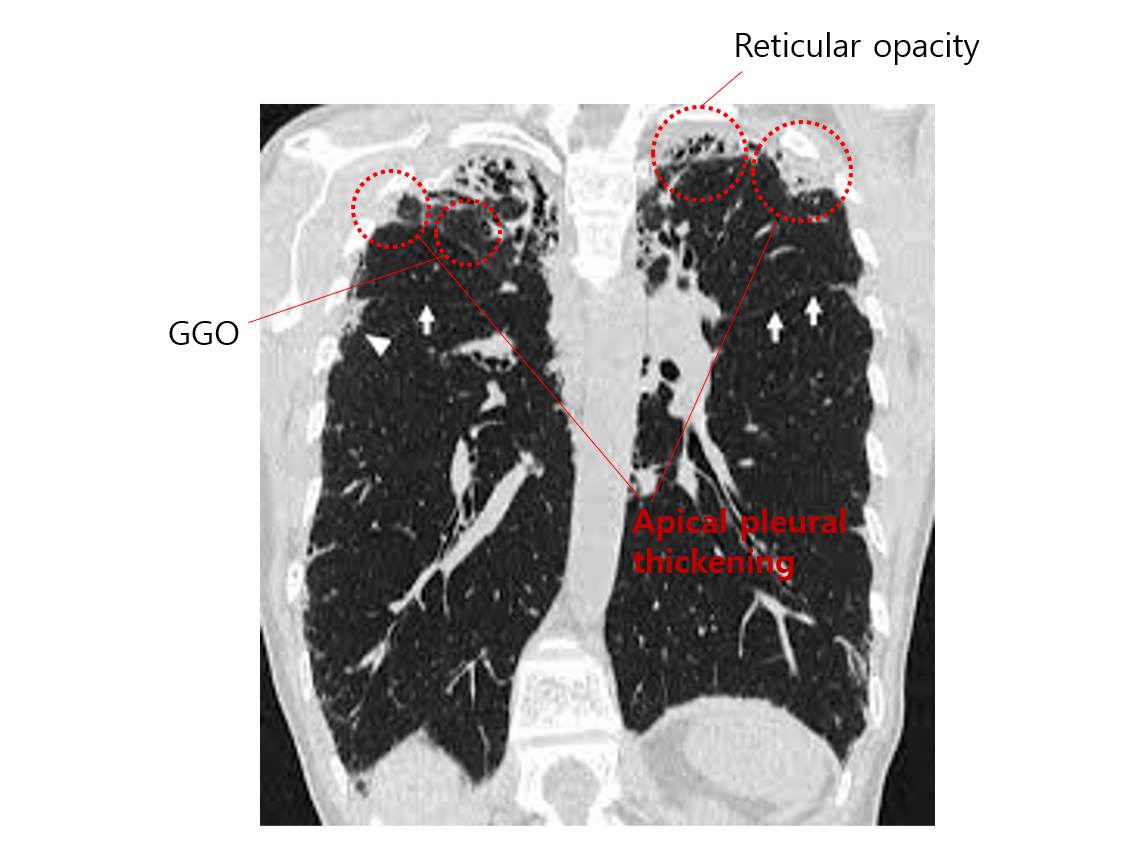

(1) 폐 apex의 pleura와 subpleural parenchyma의 섬유화가 특징적인 질환

(3) 검사소견: 폐 상엽의 pleural thickening, subpleural GGO/reticular opacity